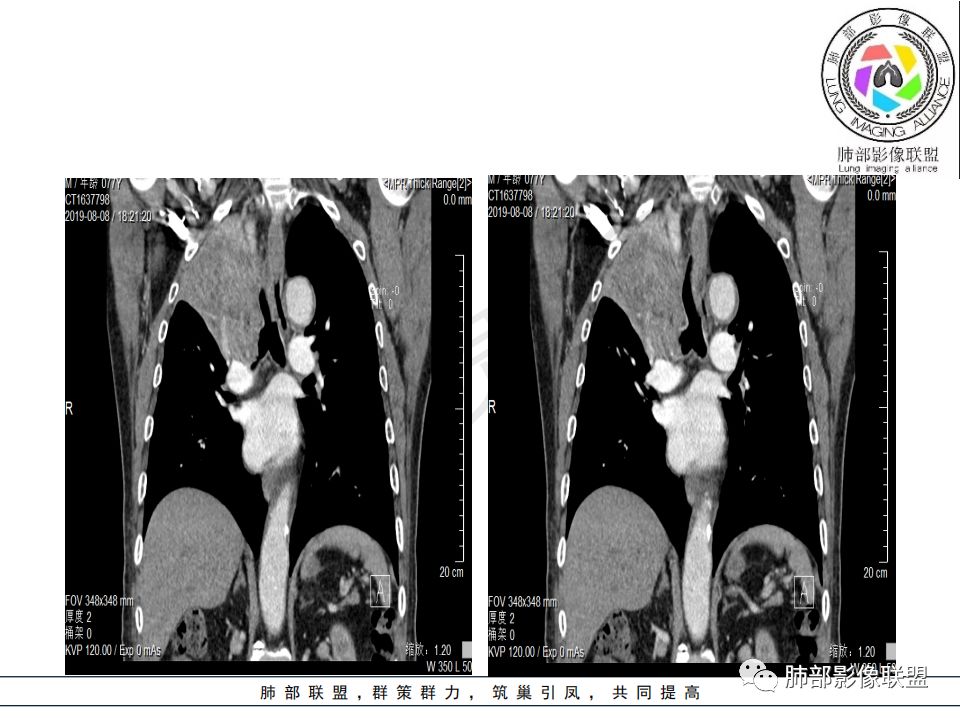

影像:影像右侧大支气管阻塞,临床没有症状或很轻微,要想到胃腺癌转移;胸壁代偿好,透亮度稍低不明显,慢性过程;34.8-52.5HU,主病灶支气管前壁另有1结节,都做成增强两期了,动脉期较平扫有强化;

诊断:多发,转移,无淋巴结及胸腔积液;

鉴别:原发鳞癌。

尘缘:

从强化情况和冠状位看主要还是从外向内的一个肿块,有不张,但不张范围不大,近端支气管堵塞,考虑腺癌或类癌(原发或转移都可能),鉴别鳞癌。